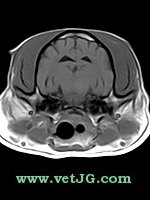

AXIAL

SAGITAL

DORSAL